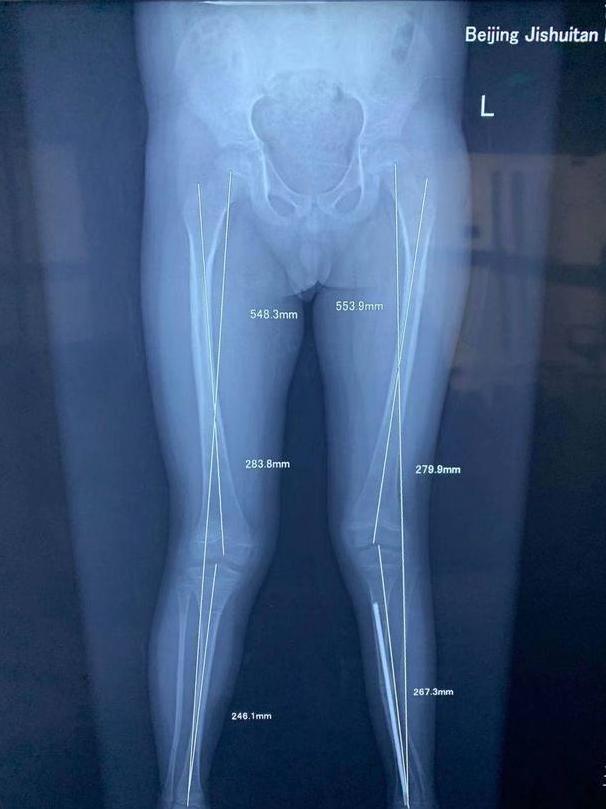

双下肢不等长的X光片

儿童双下肢不等长是小儿骨科常见的类型。原因有:外伤后骨骺异常发育、先天性双下肢发育异常、脊髓灰质炎后遗症、先天性髋关节发育异常等等。主要判断标准是影像学诊断中下肢骨骼出现绝对差值。

不等长的部位有的发生在股骨段(大腿),有的发生在胫骨段(小腿),还有一定数量的儿童股骨段和胫骨段相较于健侧均有短缩。除了不等长之外,很多还伴随有患侧肢体偏细,患侧足偏小的表现。